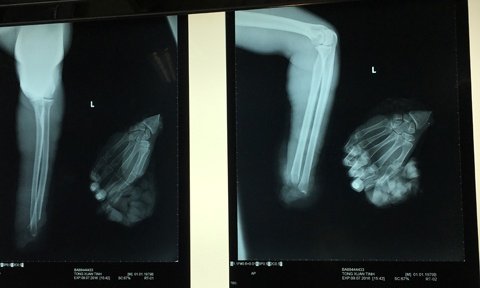

Trước đó, anh N.T.T. ở TP.HCM được người thân đưa vào Bệnh viện Chấn thương - Chỉnh hình cấp cứu trong tình trạng đứt lìa bàn tay trái. Được biết, T. là công nhân nhà máy giấy, trong lúc làm việc do bất cẩn nên bị máy xén giấy cắt đứt lìa bàn tay trái.

Tiếp nhận bệnh nhân, bác sĩ Nguyễn Văn An và bác sĩ Nguyễn Tấn Bảo Ân sử dụng kỹ thuật vi phẫu, cẩn thận cắt lọc bàn tay bị đứt, đồng thời nối gân các ngón tay. Sau đó, nối thần kinh trụ và giữa bàn tay cho bệnh nhân.

Sau 4 ngày phẫu thuật, bàn tay trái đứt lìa của anh T. đã có thể cử động nhẹ, tuy nhiên còn phải tiếp tục tập vật lý trị liệu để bàn tay có thể hoạt động bình thường.